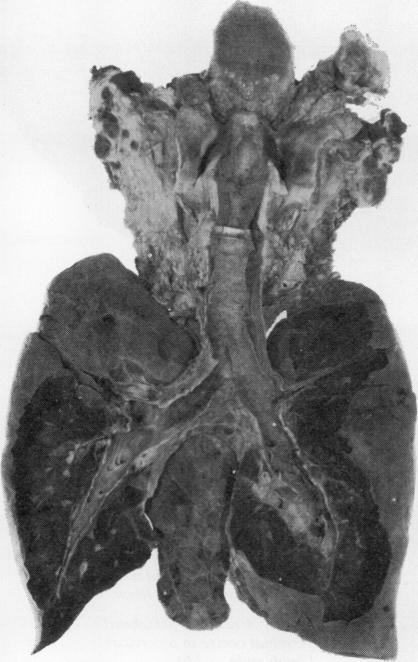

An account is given of two separate outbreaks of diphtheria amongst mentally subnormal patients and nursing staff. In a total hospital population of about 1000 the number of people involved as carriers or cases was 60 and there were five deaths. The 60 people comprised 56 patients, of whom four were involved in both outbreaks, and four nurses. The organisms isolated were C. diphtheriae mitis but five strains were non-toxigenic. It is postulated that the outbreak began following the conversion of a non-toxigenic organism to a toxigenic one by bacteriophage action. The fatal cases were examples of membranous pharyngo-laryngo-tracheo-bronchial diphtheria with well marked pseudo-casts of the upper air passages.

本文报道了智障患者及护理人员中两起独立的白喉暴发疫情。在一家约有1000人的医院中,作为带菌者或病例的涉疫人数为60人,其中5人死亡。这60人包括56名患者(其中4人参与了两起疫情)和4名护士。分离出的病原体为轻型白喉棒状杆菌,但有5株菌株不产毒素。据推测,此次暴发是由噬菌体作用使无毒菌株转变为产毒菌株所致。死亡病例均为膜性咽喉气管支气管炎型白喉,伴有明显的上呼吸道假膜。